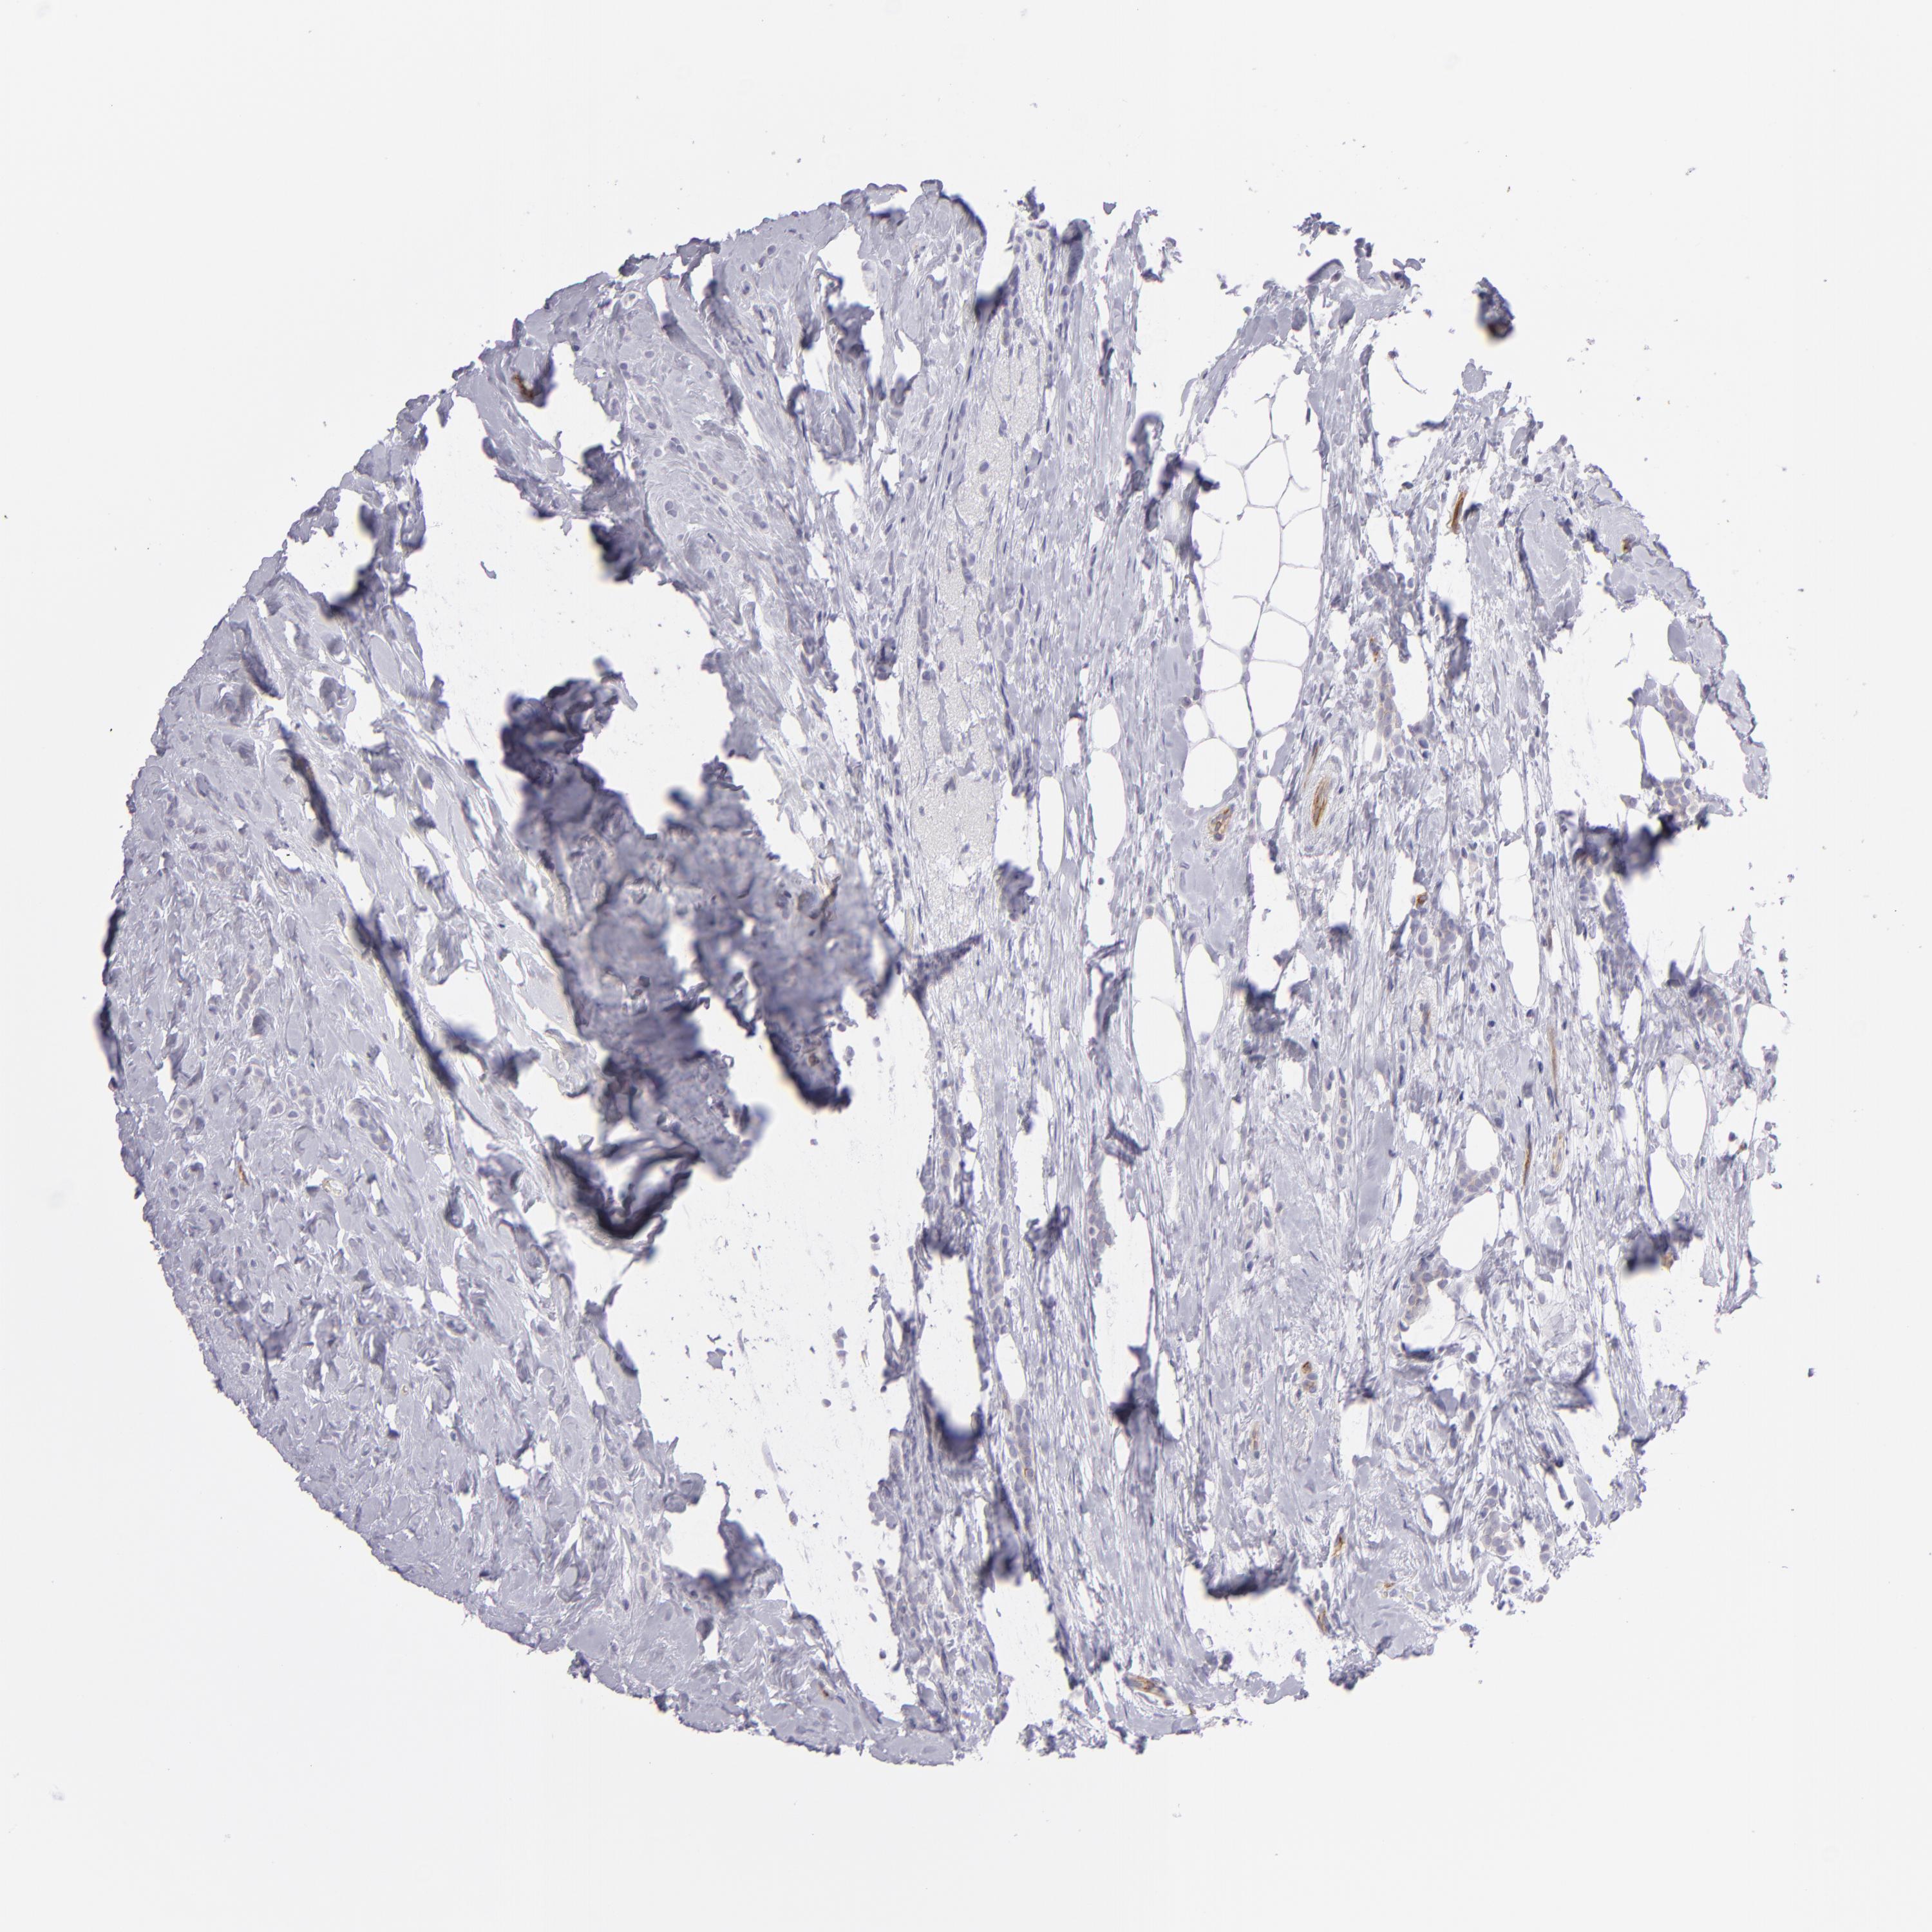

CANCER BREAST CANCER Show tissue menu

BRCA TCGA BRCA VALIDATION PROTEIN EXPRESSION

Breast cancer

Human cancer